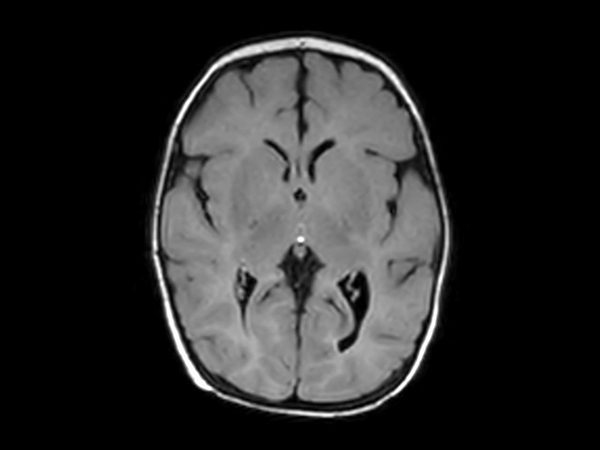

Axial T2w FLAIR with ComforTone